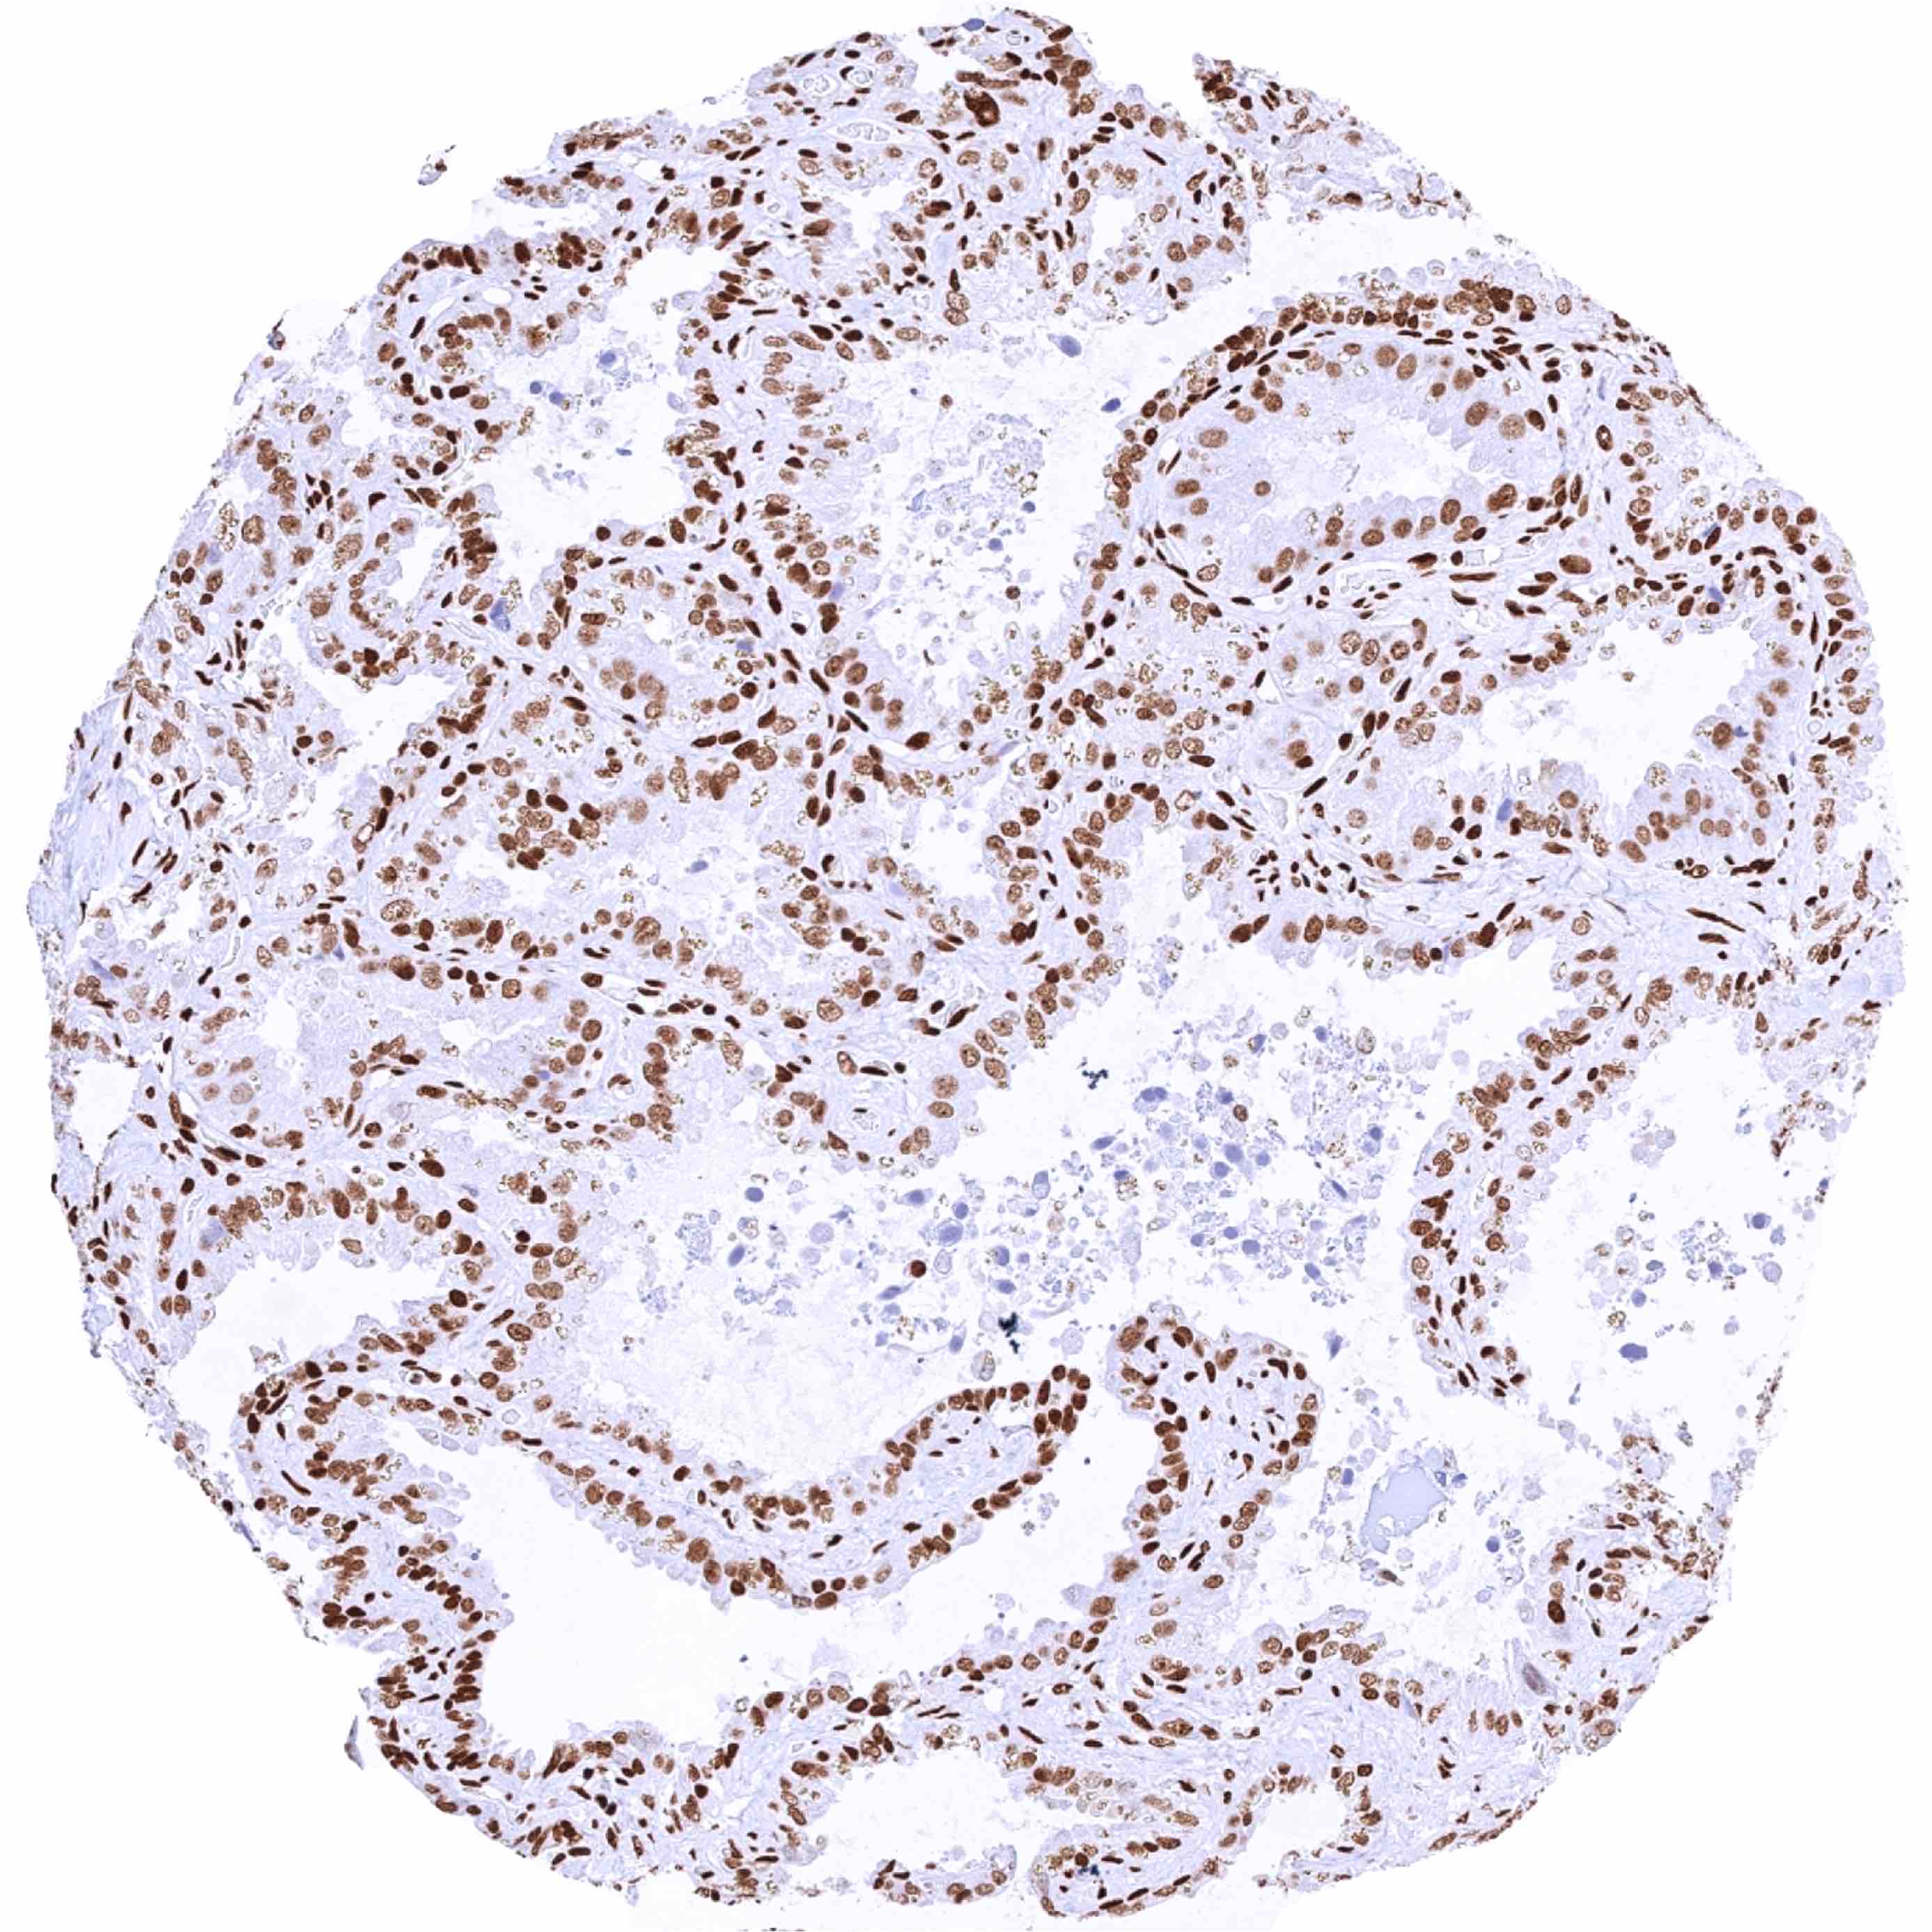

Prostate – Significant nuclear HMGB1 staining of all cells. Staining is particularly low in acinar cells and highest in basal cells